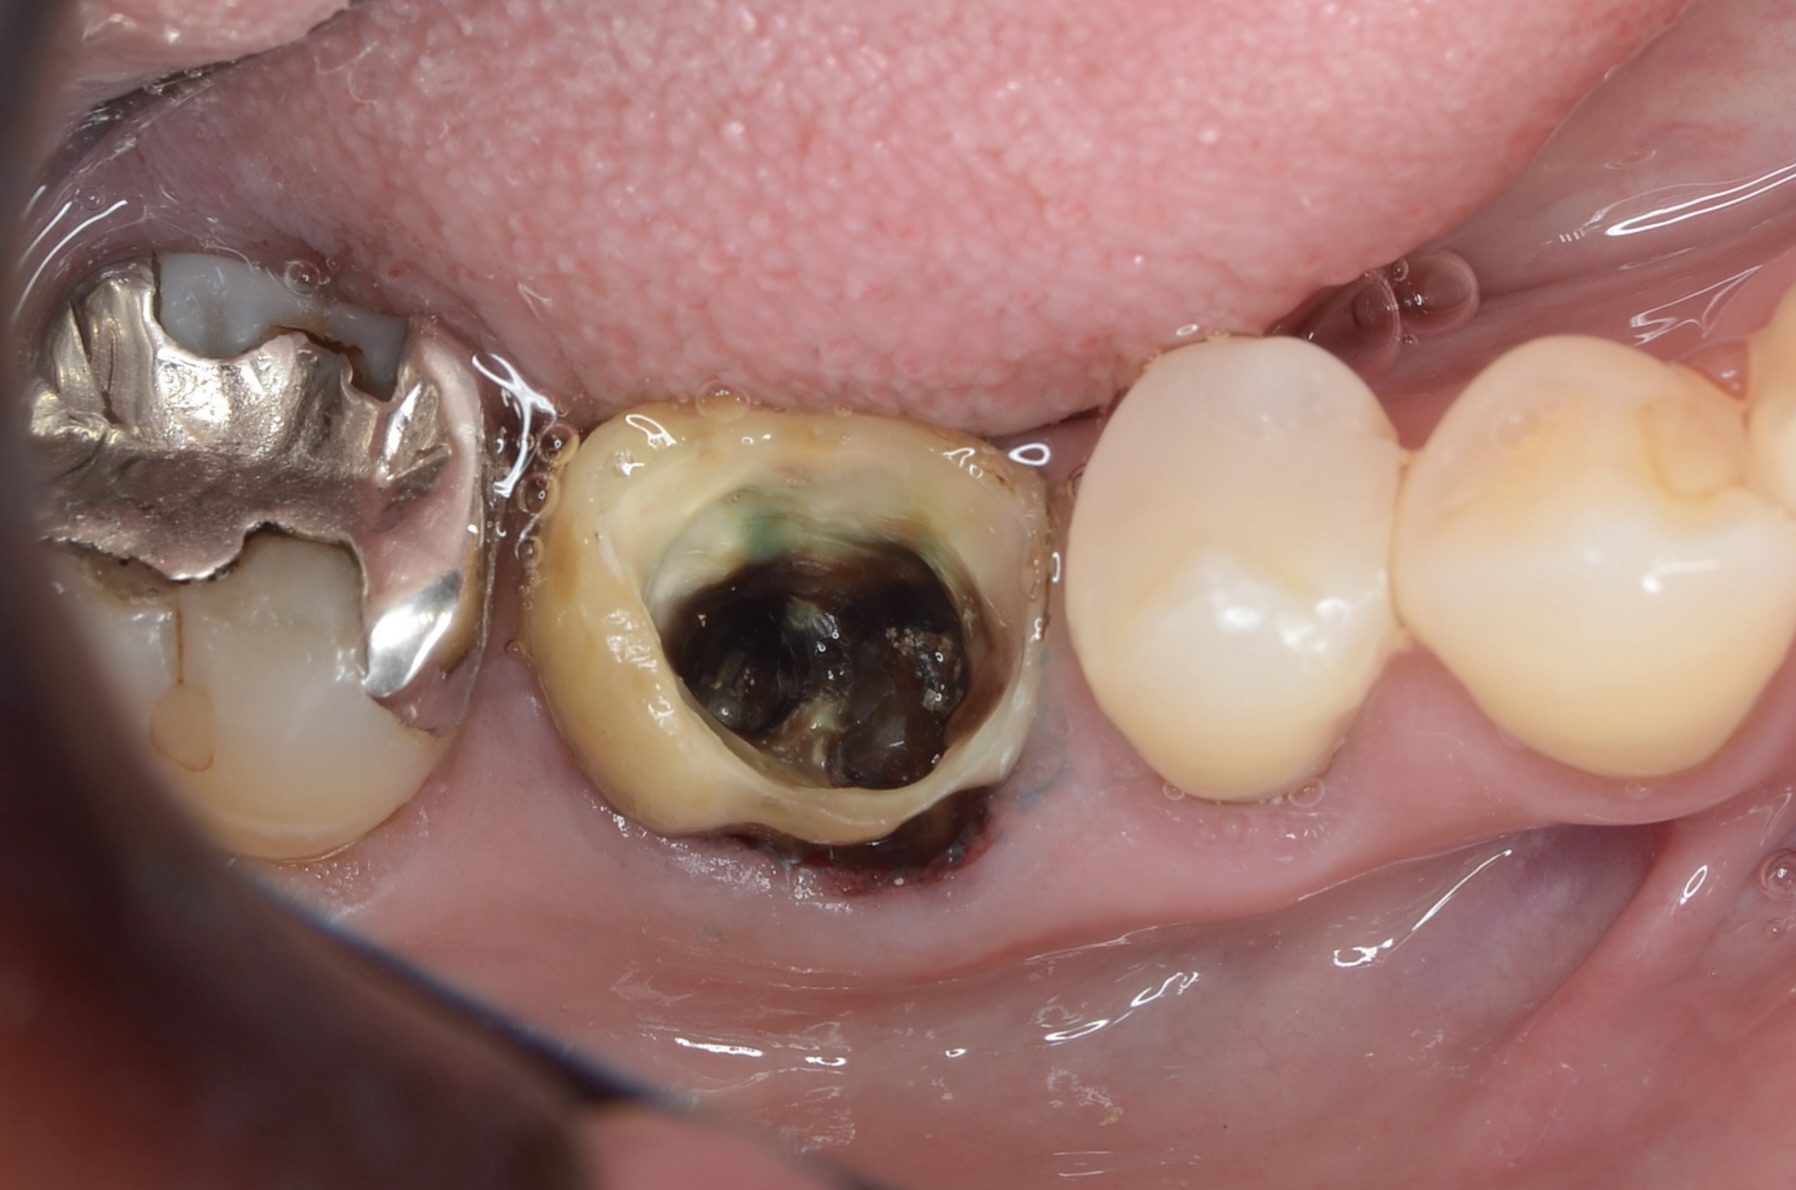

レジンコア除去後

-

歯頸部の歯肉縁下にまで虫歯が広がっていました。 通常であれば、抜歯になります。 -

隔壁

一旦、穴を塞ぎラバーダムがかけられるようにレジンで隔壁を作成します。その後根管治療を行います。 -